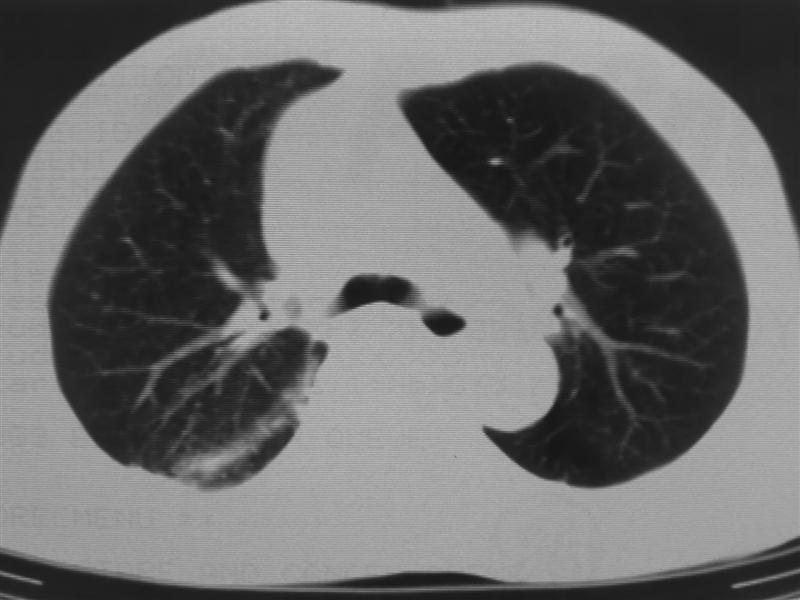

标题: CT10080:F76Y,各位老师发表高见!!! [打印本页]

标题: CT10080:F76Y,各位老师发表高见!!!

支持右下肺癌伴肺内转移

右下肺周围型肺癌伴双肺右侧叶间 胸膜及右肺门淋巴结转移

考虑:肺癌伴肺、胸膜 纵隔淋巴结转移可能性大!